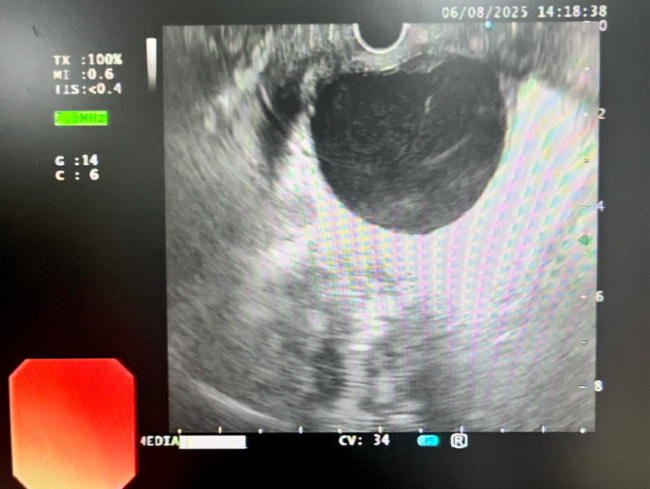

近日,51岁的王叔叔因腹痛呕吐3天入住我院消化内科,经完善相关检查后,磁共振【上腹部MRI平扫】提示:1.胰腺信号异常,多考虑:慢性胰腺炎急性发作。2.胰头颈区囊性病变,多考虑包裹性坏死。3.胰体囊性灶(囊腺瘤可能);【超声胃镜检查】提示:1.慢性胰腺炎,胰管多发结石2.胰头颈部囊性病灶(假性囊肿可能)3.浅表性胃窦炎